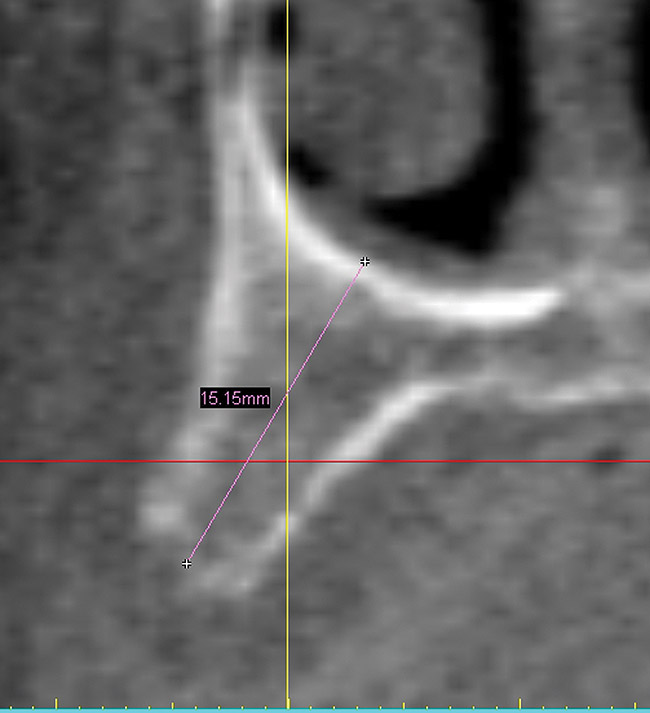

A 56-year-old woman in good health presented with recent extractions and a fully edentulous maxillary arch and edentulous posterior mandibular areas. A CBCT scan 3D view revealed large osseous defects in the maxillary arch that required grafting before implant placement (Figure 1). The treatment plan was made for maxillary ridge augmentation followed by fixed prosthesis-supported dental implants in all of the edentulous areas. The mandible did not require grafting. The patient was wearing a full upper denture during the entire grafting and subsequent implant healing time period. The maxillary arch showed large defects on the axial view of the CBCT (Figure 2). A cross-sectional CBCT view also showed deficient height of bone with a vertical height of 9.7 mm (Figure 3). Upon full-thickness reflection, large deficient areas of the ridge were seen that required grafting before implant placement (Figure 4).

Figure 3  Cross-sectional view showing large defect with 9 mm of remaining bone.

Figure 3

Figure 8  Six-month post-graft CBCT cross-sectional view showing 5 mm of bone growth vertically.

Figure 8